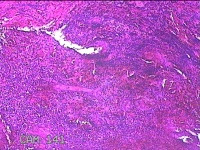

左耳部肿物

性别

男

年龄

24岁

临床诊断

一般病史

左耳部肿物1周。

标本名称

大体所见

灰白暗红色肿物1.3x1.2x0.2cm一个,表面糜烂。